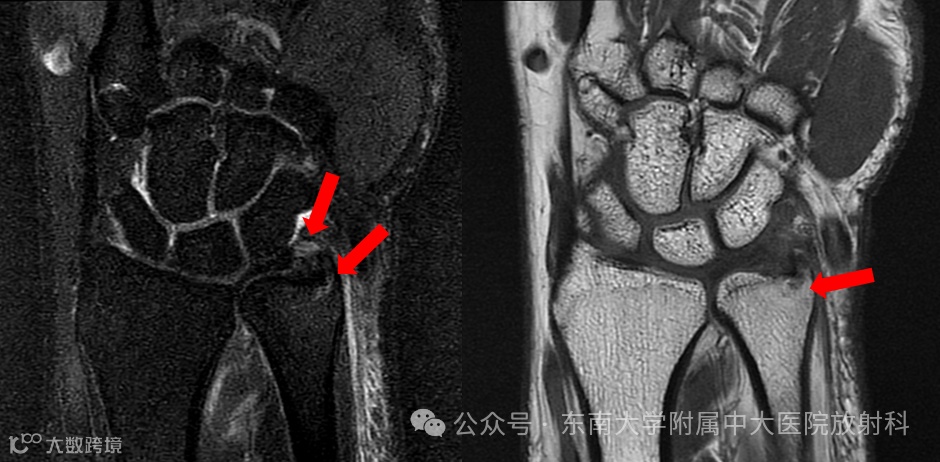

病例2

女 ,63岁

主诉:右腕关节疼痛1年

病史:患者1年余前出现右腕关节疼痛,予保守治疗,至今症状未缓解

专科检查:右腕关节稍肿胀、压痛

影像号:3396554,2025-04-01,右腕关节MRI平扫

影像学表现